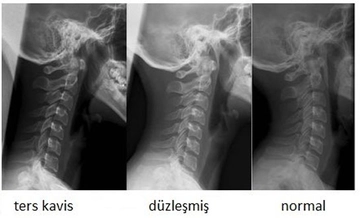

Tanı YöntemleriBeyin omurilik sıvısı akması şüphesi durumunda, çeşitli tanı yöntemleri kullanılmaktadır: